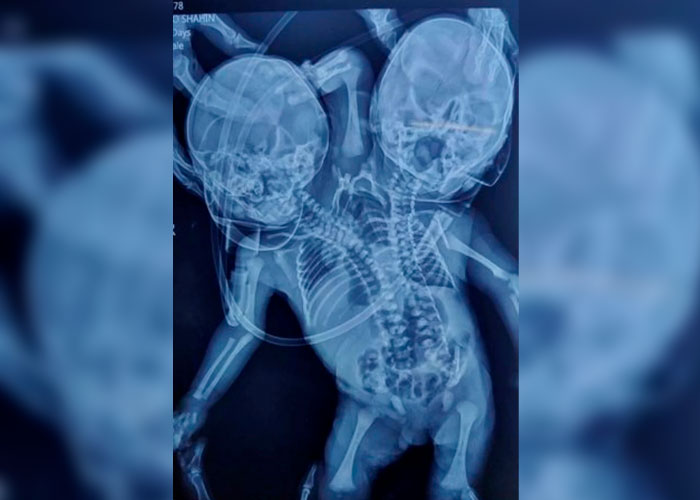

Atónitos quedaron los médicos tras el nacimiento de un bebé con dos cabezas, tres brazos y dos corazones en el estado Madhya Pradesh, en la India

Shaheen Khan y su esposo Sohail esperaban mellizos, pero se sorprendieron cuando ella dio a luz a un bebé con dos cabezas, tres manos y dos corazones, el 28 de marzo en Ratlam, en el estado indio de Madhya Pradesh.

La rara condición es conocida en el ámbito médico como parapagus dicefálico, donde dos bebés están unidos por un torso; y en este caso no se había detectado antes del nacimiento.

No está claro a partir de los informes si se considera un nacimiento de gemelos unidos o un niño. Los informes en la India lo describen como un bebé; pero la condición se considera una forma rara de gemelos parciales. La tercera mano está hacia atrás entre las dos caras.

Los gemelos que nacen con dos cabezas; pero que comparten un cuerpo, se conocen como parápagos dicefálicos, una manera extremadamente inusual de unión que se dice que afecta solo a uno en un millón de nacimientos.